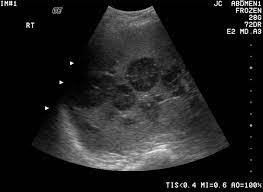

Ultrasound is often one of the first line tests in the detection of cancer. Keep in mind, however, that an ultrasound alone cannot make the diagnosis of cancer. Ultrasounds can produce false positives. Thyroid nodules are lumps that can appear in the thyroid gland in front of the throat. They increase with age and, in fact, if you look with sensitive measures like ultrasound, over 50% of people will have thyroid nodules by the age of 50 or 60. This test will usually help determine that the nodule has a low chance of being cancerous (has characteristics of a benign nodule), or that it has some characteristics of a cancerous nodule, and therefore a biopsy is indicated. Ultrasounds are not useful for treatment monitoring. While it can't diagnose cancer, it can detect the abnormal tissues that may possibly be cancerous. A small transducer (probe) both transmits sound waves into the body and records the waves that echo back. My 3.8 year old's neck ultrasound shows chain of lymph nodes bilaterally with largest on right 14mm by 6mm and largest on left 13mm by 6mm,the left one is there since a year.few intraparotid largest 5mm.thyroid & both submandibular normal. Staging head and neck cancers The most common symptom of thyroid cancer is a hard lump on the neck—but most patients experience no symptoms at all. Doctors often use them to guide a needle during a biopsy.

Ultrasound imaging can help determine the composition of lump, distinguishing between a cyst and a tumour. The survival rate in this type of cancer can be as high as 90 percent provided it is detected early in stage i itself. Throat cancer can develop in any part of the throat. The ultrasound can help to show whether a cyst has any solid areas as it is more likely to be cancer. Two in three cases of thyroid cancer occur in people under age 55, and 75%.